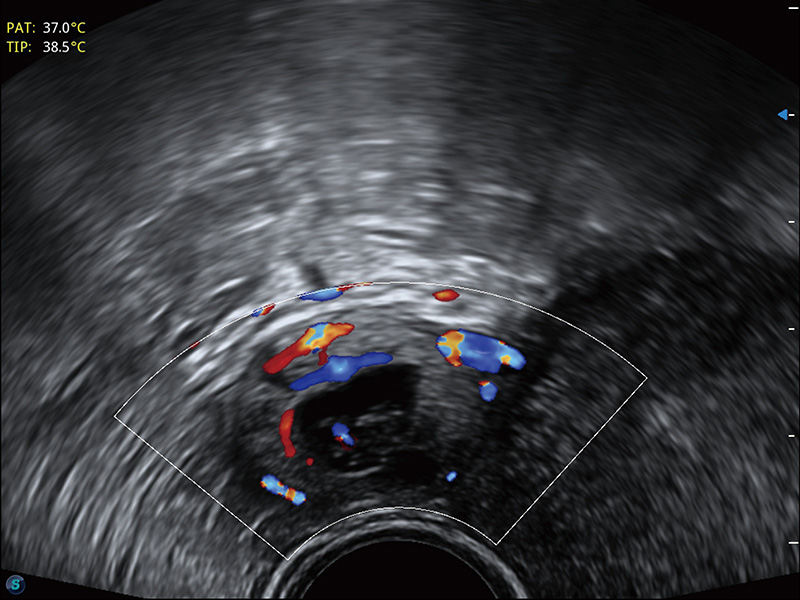

“生育问题”即关系民族复兴,也关系亿万家庭的幸福。随着婚育年龄推迟、社会压力增加等因素,越来越多人群也面临着“生不出、生不好”的问题。辅助生殖作为治疗不孕不育最有效的方法之一,也逐渐成为育儿新希望。而超声检查能为生殖需求人群的初诊评估提供宝贵的信息。 P20 Elite是狗万官方网站匠心打造的一款生殖应用型彩超。她继承狗万官方网站高端极光平台,突破性地将多款新型芯片及硬件模块进行整合,均衡了高端系统性能与小巧灵动机身。P20 Elite卓越的图像质量搭载专科探头,旨在为您提供全面的辅助生殖解决方案。

P20 Elite配备了丰富的生殖探头群和临床应用功能,在卵泡监测、穿刺取卵、胚胎移植、妊娠确认等领域,为生殖需求人群提供了新的临床机会,重新定义高端超声如何应用于生殖健康检查。

耦合剂加热器可将耦合剂维持在舒适的温度,体现患者关爱。